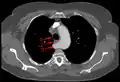

Aberrant subclavian artery at axial CT-scan. (1) trachea, (2) esophagus, (3) Aberrant subclavian artery.

Aberrant subclavian artery at axial CT-scan. (1) trachea, (2) esophagus, (3) Aberrant subclavian artery. Aberrant right subclavian artery at angiography.